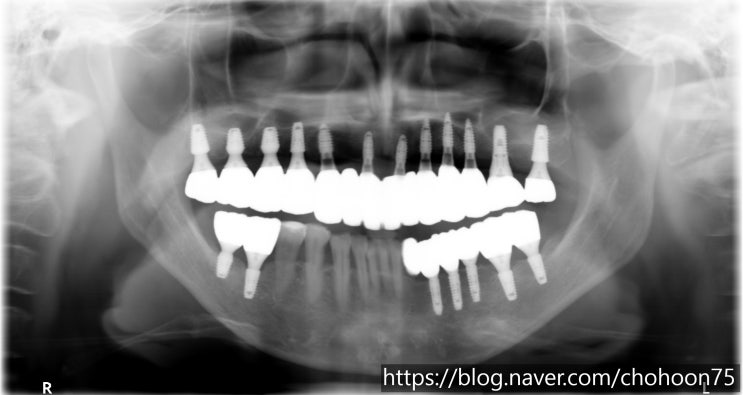

[조훈치과] 임플란트 치료를 통한 교합 관계 회복

안녕하세요. 조훈 치과입니다. 치아를 상실한 채 오랜 기간 방치를 하게 되면 치아 간의 높낮이의 변화가 ...